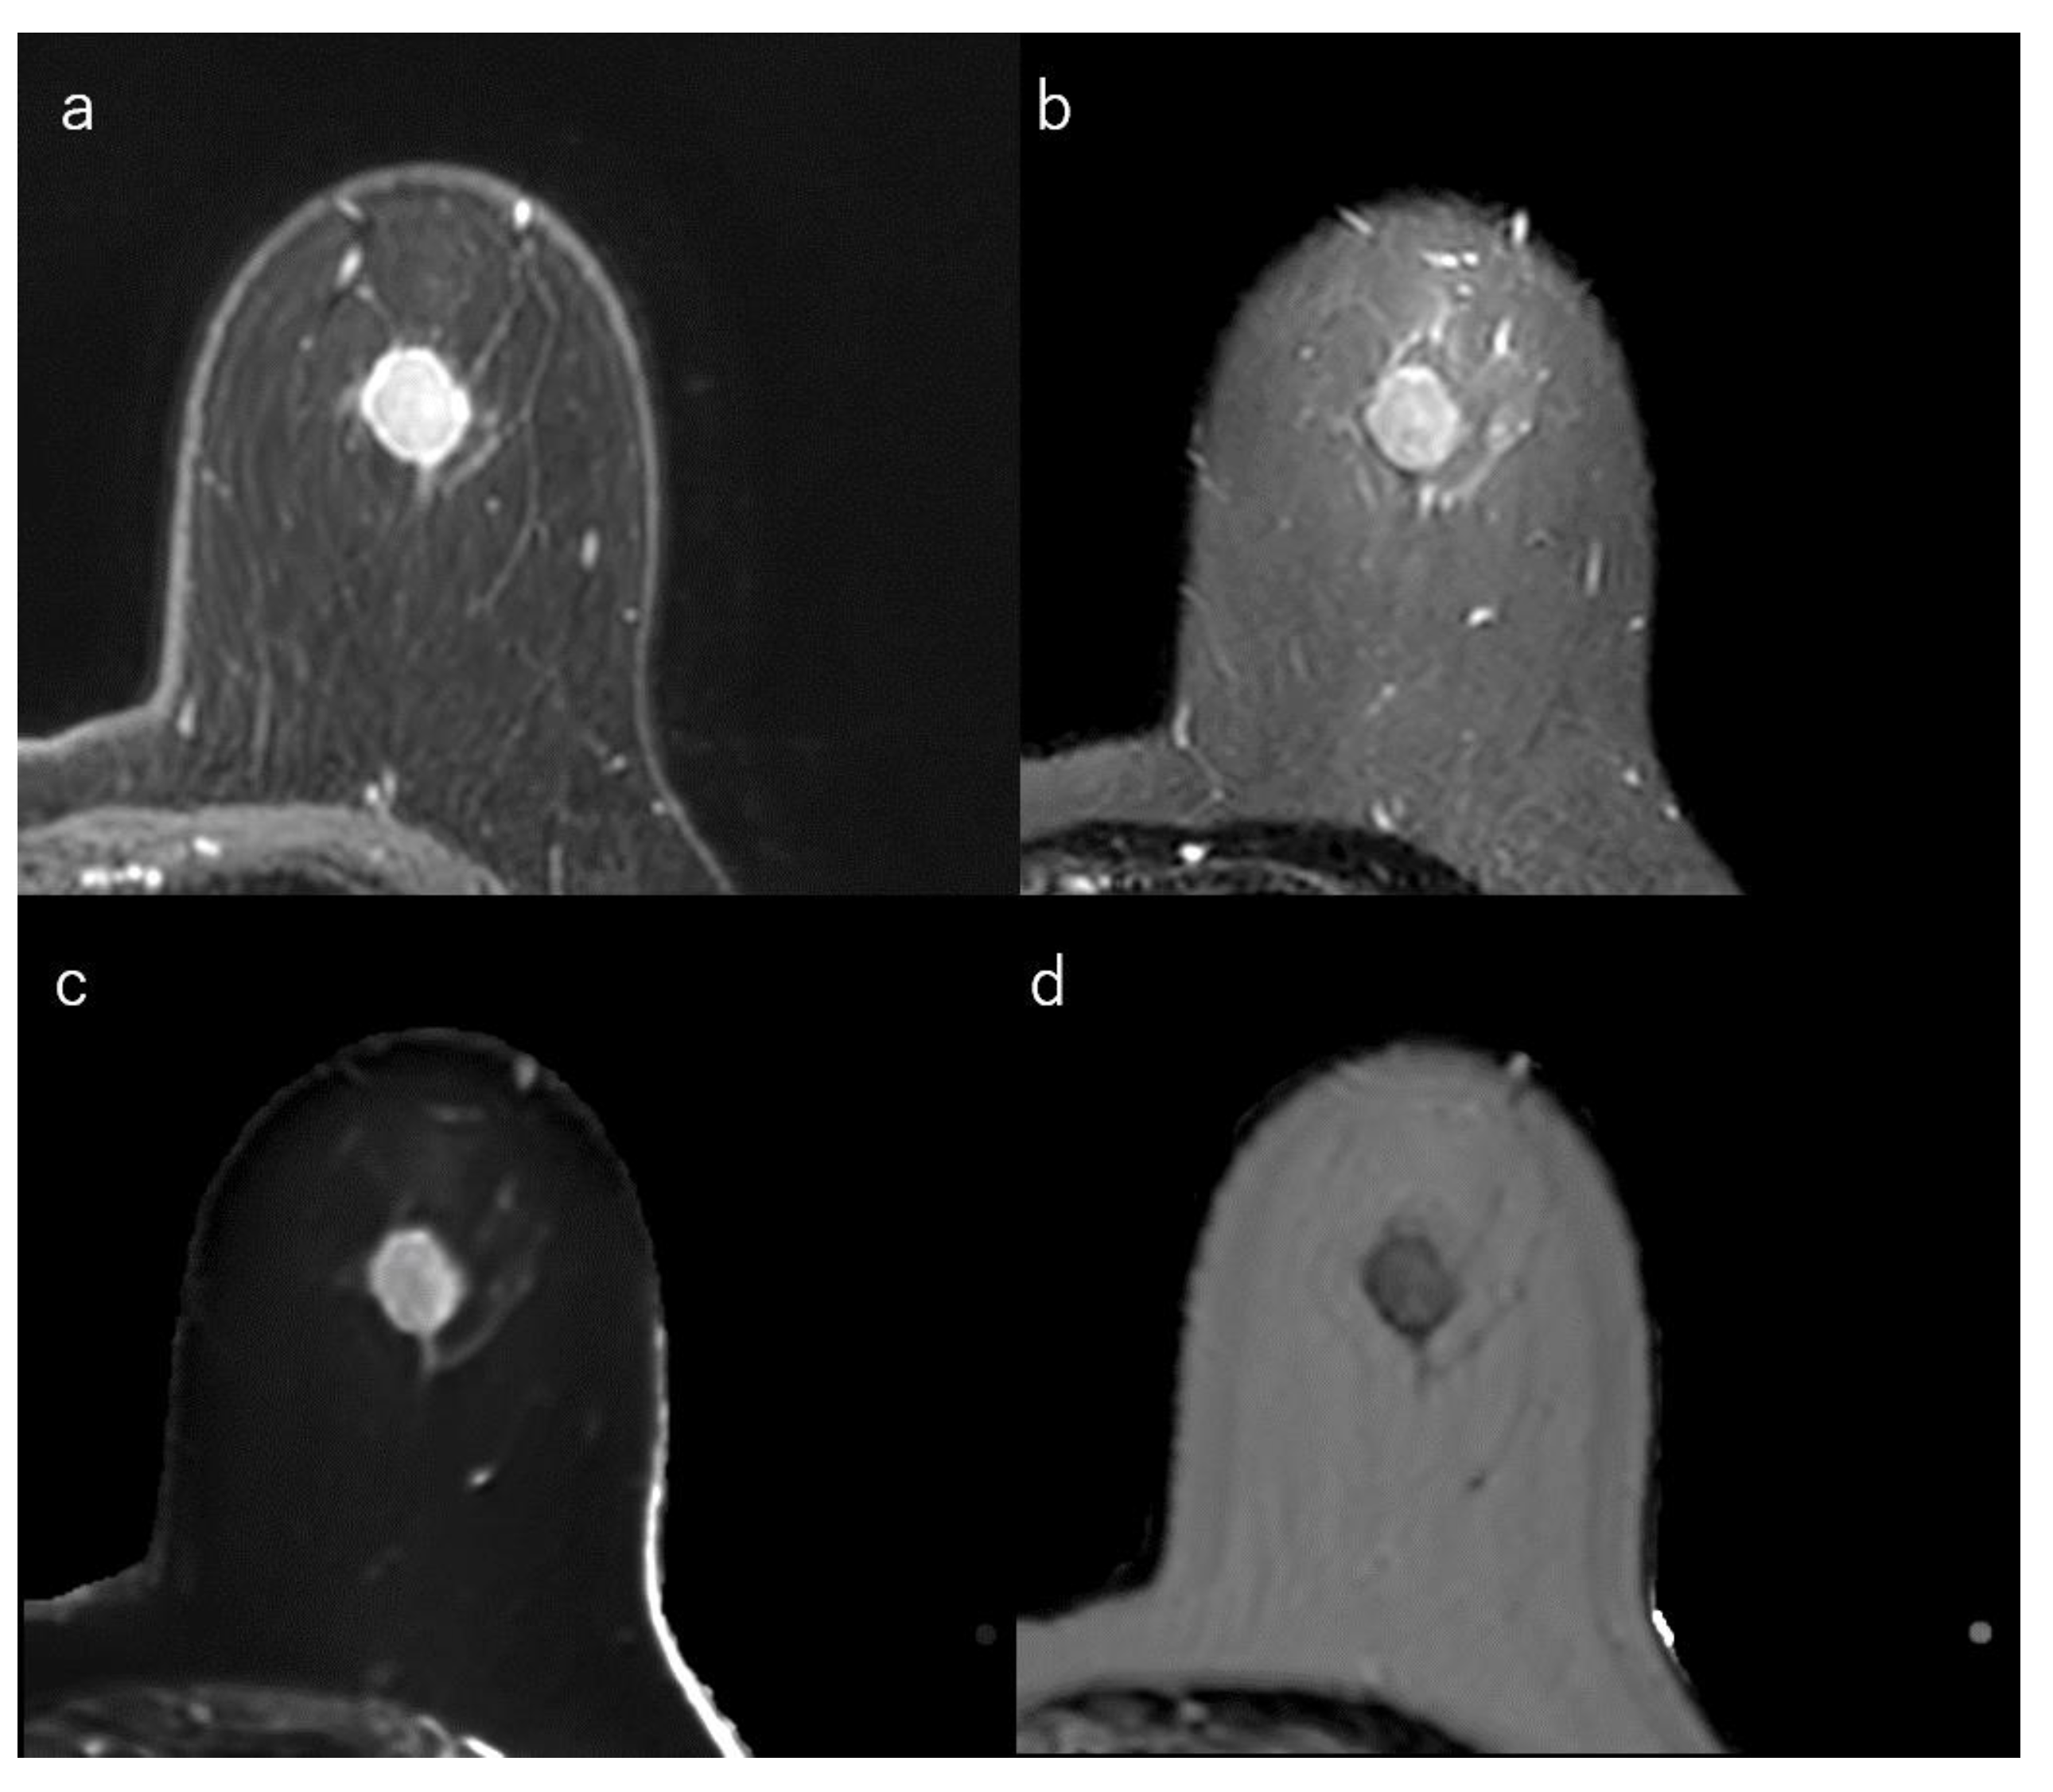

Figure 4.

(a) Dynamic contrast-enhanced MR image in a 32-year-old woman with luminal-B type breast cancer shows a heterogeneously enhanced oval mass with rim enhancement. (b) Short-tau inversion recovery image shows an intermediate signal mass. (c) T1 map (window width/centre = 1400/2400 ms) shows an intermediate signal mass; Mean T1 of the mass is 1174 ms on T1 map. (d) T2 map (window width/centre = 160/240 ms) shows an intermediate signal mass; mean T2 of the mass is 97 ms on T2 map.

Tumour roundness is positively correlated with Ki-67 index [154]. Luminal-B subtypes are more often associated with multicentric/multifocal disease than are luminal-A cancers [32,156,157] and are also enriched for fibroblast growth factor receptor gene amplification, which has been implicated in angiogenesis [33,158]. This may lead to a higher ratio of lesion enhancement on DCE-MRI and heterogeneous internal enhancement [32,33,41,159] (Figure 4).